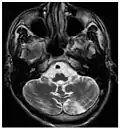

-

Die axiale MRT des Gehirns eines 27-jährigen Morbus-Fabry-Patienten mit ischämischem Schlaganfall zeigt den Schlaganfall in der linken zerebellären Hemisphäre. Der Patient wies sonst keine Symptome der Erkrankung auf. -